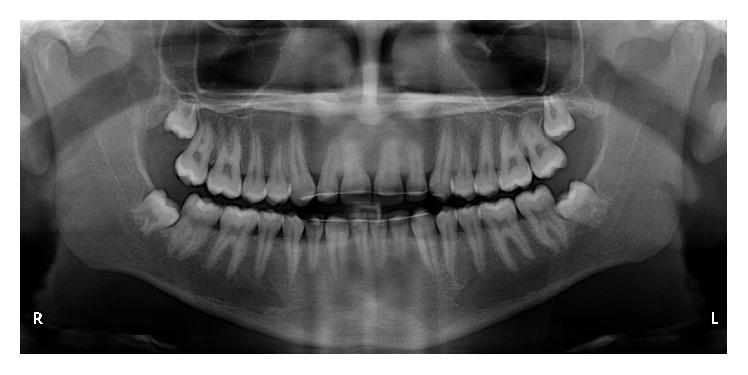

Bilateral mandibular tooth transposition is a relatively rare dental anomaly caused by distal migration of the mandibular lateral incisors and can be detected in the early mixed dentition by radiographic examination. Early diagnosis and interceptive intervention may reduce the risk of possible transposition between the mandibular canine and lateral incisor. This report illustrates the orthodontic management of bilateral mandibular canine-lateral incisor transposition. Correct positioning of the affected teeth was achieved on the left side while teeth on the right side were aligned in their transposed position. It demonstrates the outcome of good alignment of the teeth in the dental arch.

双侧下颌牙齿易位是一种相对罕见的牙齿异常,由下颌侧切牙向远中移位引起,可通过影像学检查在混合牙列早期发现。早期诊断和阻断性干预可能会降低下颌尖牙和侧切牙之间可能发生易位的风险。本报告阐述了双侧下颌尖牙-侧切牙易位的正畸治疗。左侧患牙实现了正确定位,而右侧牙齿则在其易位位置排齐。它展示了牙弓中牙齿良好排齐的效果。